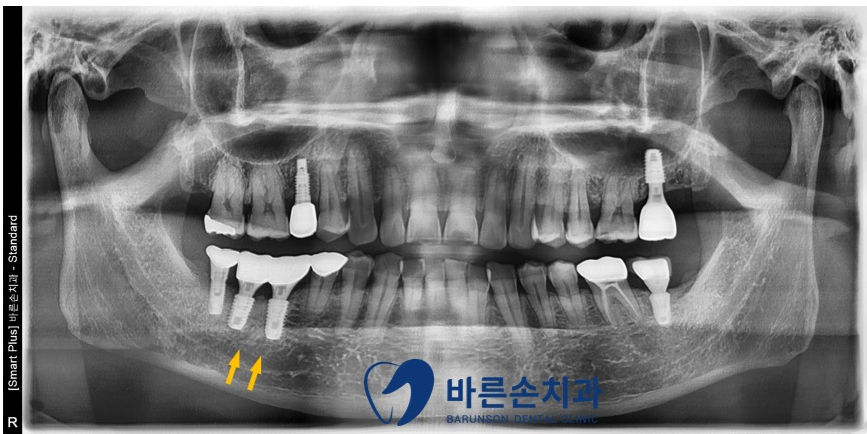

뼈이식 후 경과 관찰

임플란트 제거, 뼈이식 후 사진입니다.

3개월 정도 기다리면, 이식된 뼈가

단단하게 굳어 임프란트를 새로 할 수 있습니다.